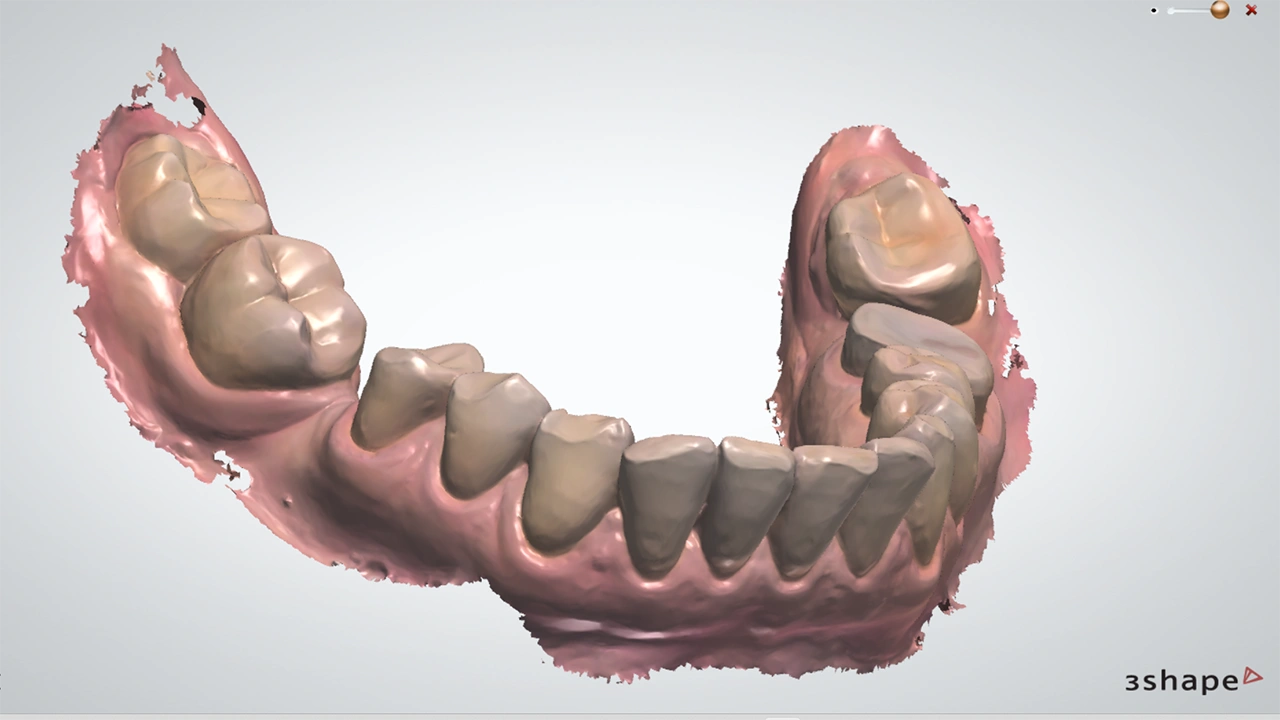

Цифровые слепки: конец «эпохи ложек»

Внутриротовой сканер (IOS) заменяет классические слепки. За несколько минут он создаёт 3D-модель зубов с точностью, которая не только не уступает, а часто и превосходит по качеству полученную аналоговым методом.

Систематический обзор Pesce P. et al., (2025) подтверждает: цифровые слепки в большинстве случаев дают равноценную или более высокую точность, особенно при сканировании под одиночные коронки или мостовидные протезы небольшой протяжённости.

А самое главное — это комфорт для пациента. В метаанализе Pachiou A. et al., (2025) показано, что цифровые слепки значительно снижают дискомфорт, тревожность и неприятные ощущения по сравнению с классическими, особенно при протезировании на имплантатах.

Ограничения

Конечно, не всё идеально. На полной дуге челюсти возможны погрешности из-за «накопления ошибок» во время сканирования. Качество сканера, освещение, опыт персонала, попадание слюны — всё это влияет на результат. В некоторых сложных случаях классические аналоговые методы всё ещё остаются золотым стандартом.